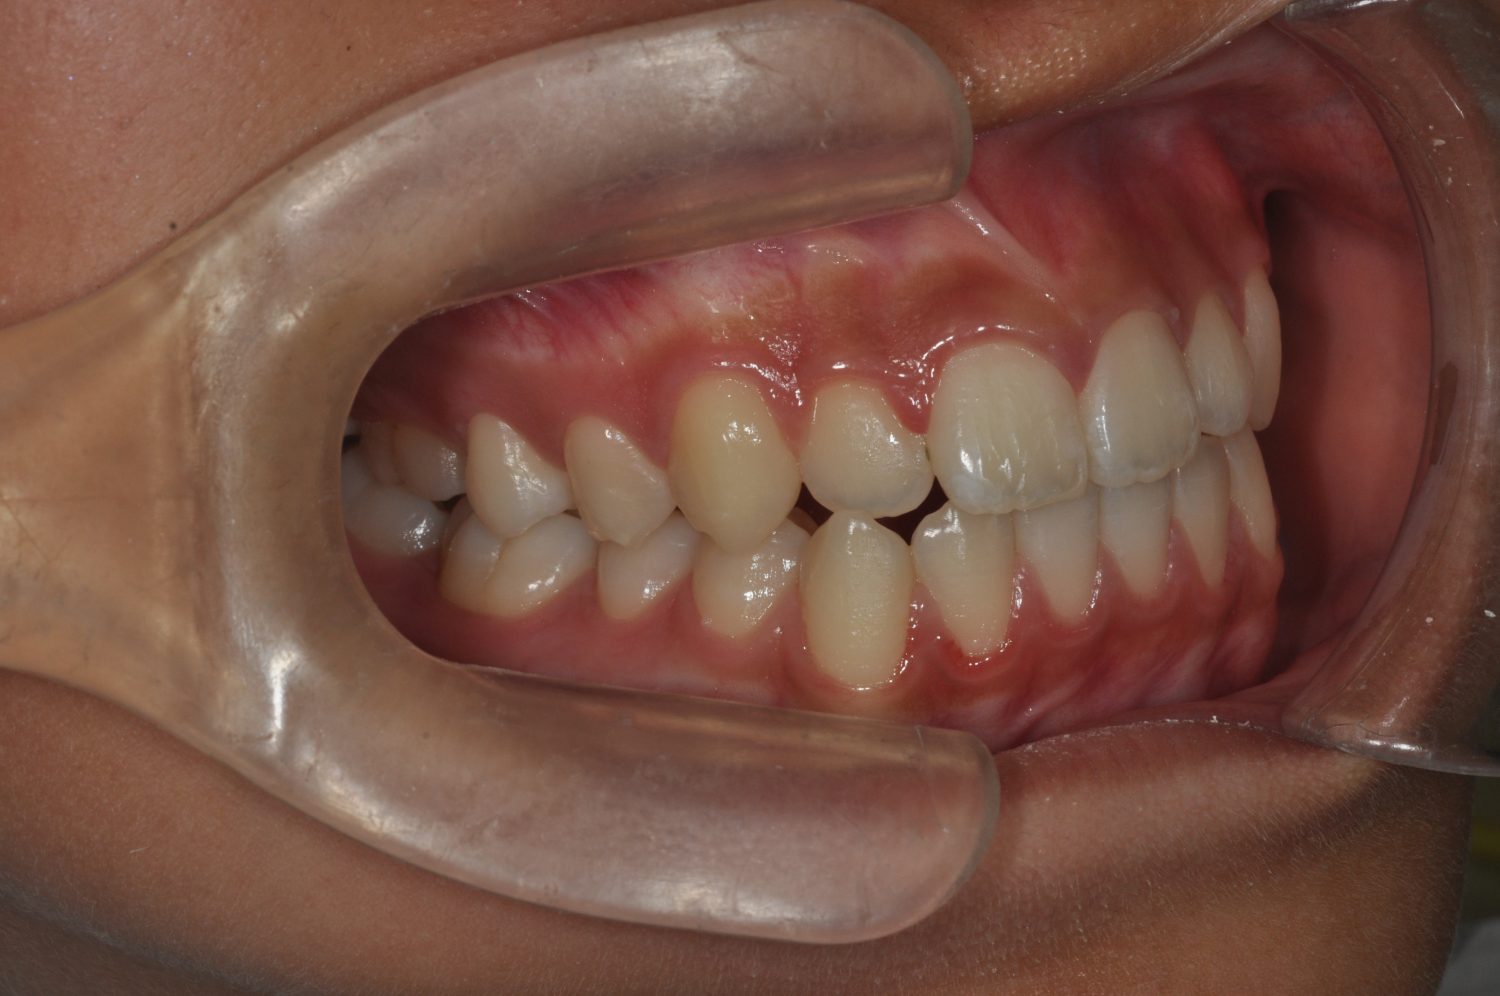

| 主訴 | 口上下顎のガチャガチャが気になる |

| 治療内容 | 歯冠幅径が大きいことから、IPRを併用した非抜歯治療 |

| 想定されたリスク | 矯正中の清掃状況によってはむし歯や歯周病のリスクがありました。歯根吸収や歯肉退縮のリスクもありました。 |

Ⅰ期治療で前歯部反対咬合をセクショナルアーチとMPAを使用して改善した後、成長観察を行っていました。永久歯が萌出したため、Ⅱ期治療を開始することとなった。上下顎とも骨格的に問題がなかったため、非抜歯で治療を行った。